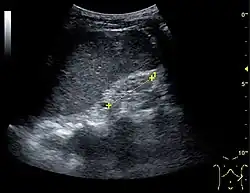

Ultrasound

Kidney ultrasonography is useful for diagnostic and prognostic purposes in chronic kidney disease. Whether the underlying pathologic change is glomerular sclerosis, tubular atrophy, interstitial fibrosis, or inflammation, the result is often increased echogenicity of the cortex. The echogenicity of the kidney should be related to the echogenicity of the liver or the spleen. Moreover, decreased kidney size and cortical thinning are often seen, especially when the disease progresses. However, kidney size correlates to height, and short persons tend to have small kidneys; thus, kidney size as the only parameter is unreliable.[63]

Chronic renal disease caused by glomerulonephritis with increased echogenicity and reduced cortical thickness. Measurement of kidney length on the US image is illustrated by '+' and a dashed line.[63] -